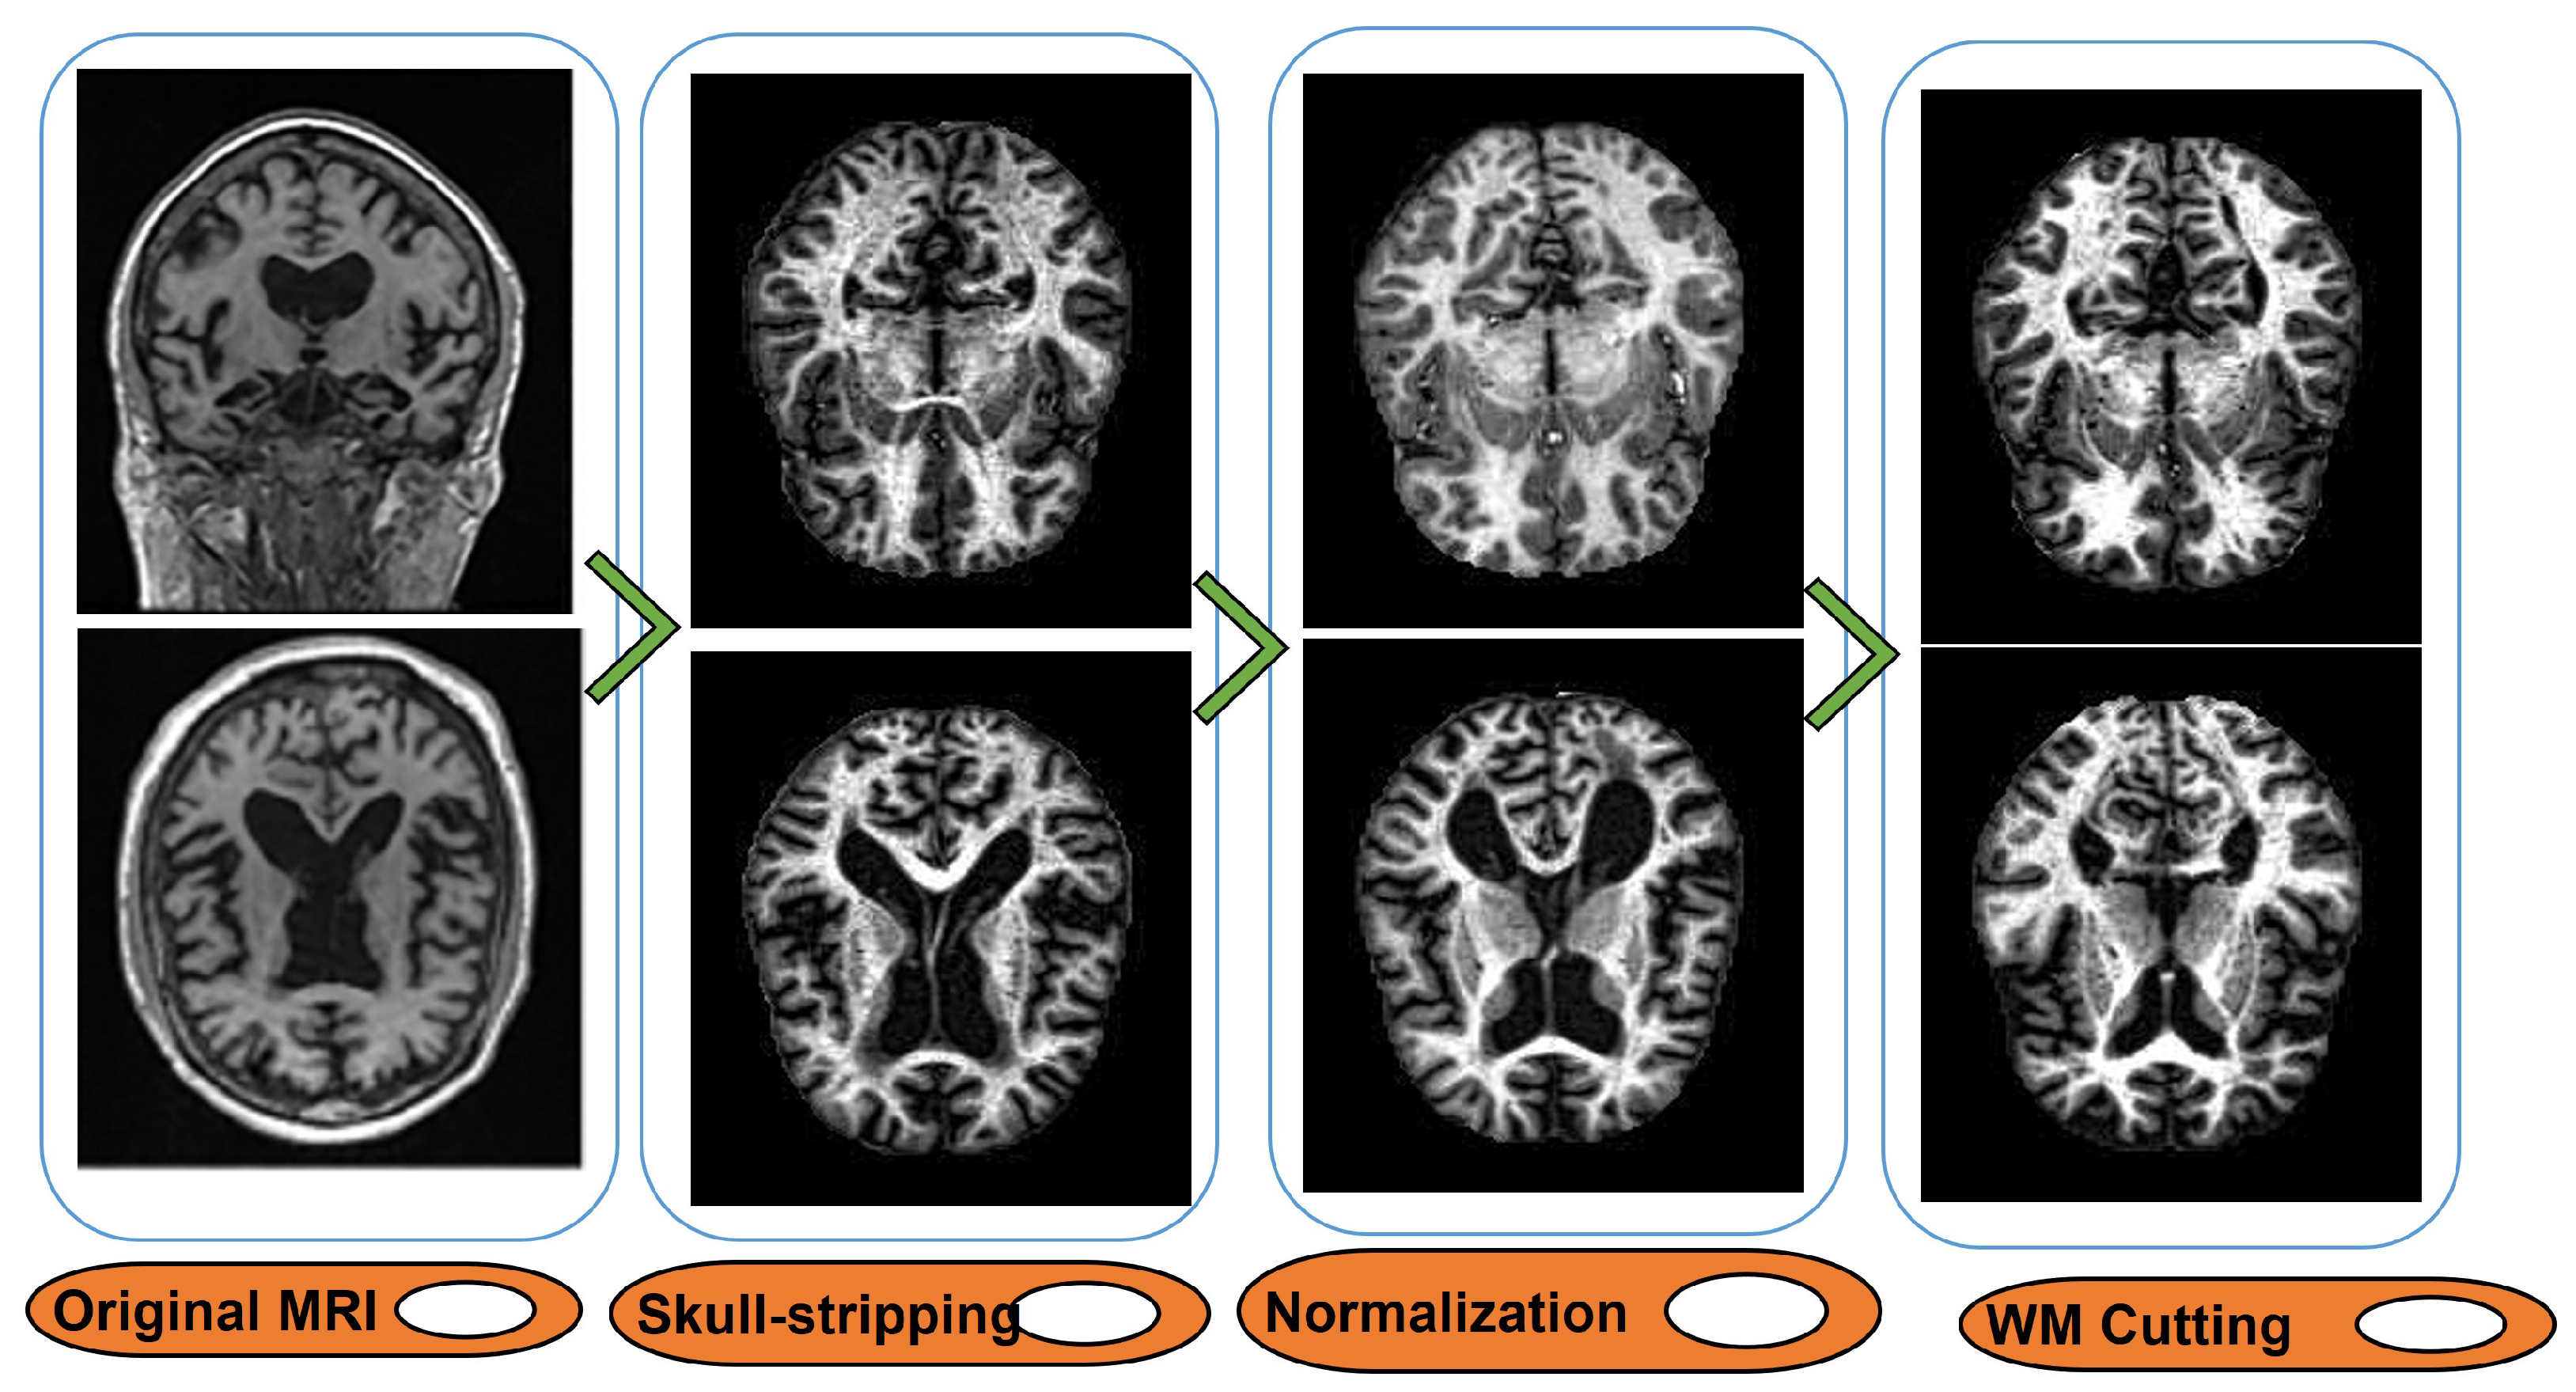

- Select structural MRIs that were labeled with MPRAGE because they were thought to be the highest quality images.

- Filter the collected MRIs with the recent images of each subject.

- Perform skull-stripping for each selected MRI, and then, use the FLIRT package to affine MRI to the global brain map model space (i.e., MNI152).

- Scan and register individuals MRI by eliminating any spatial variances

- Normalize and resize MRI to the dimension of 145 × 172 × 145.

- Recover the white matter (WM) region of the MRI images (a sample of pre-processed MRI is given in Figure 3).

Figure 3. MRI processing method. - Co-register the standardized image associated with the first functional PET scan (with T1 weight) with its correspondence MRI.